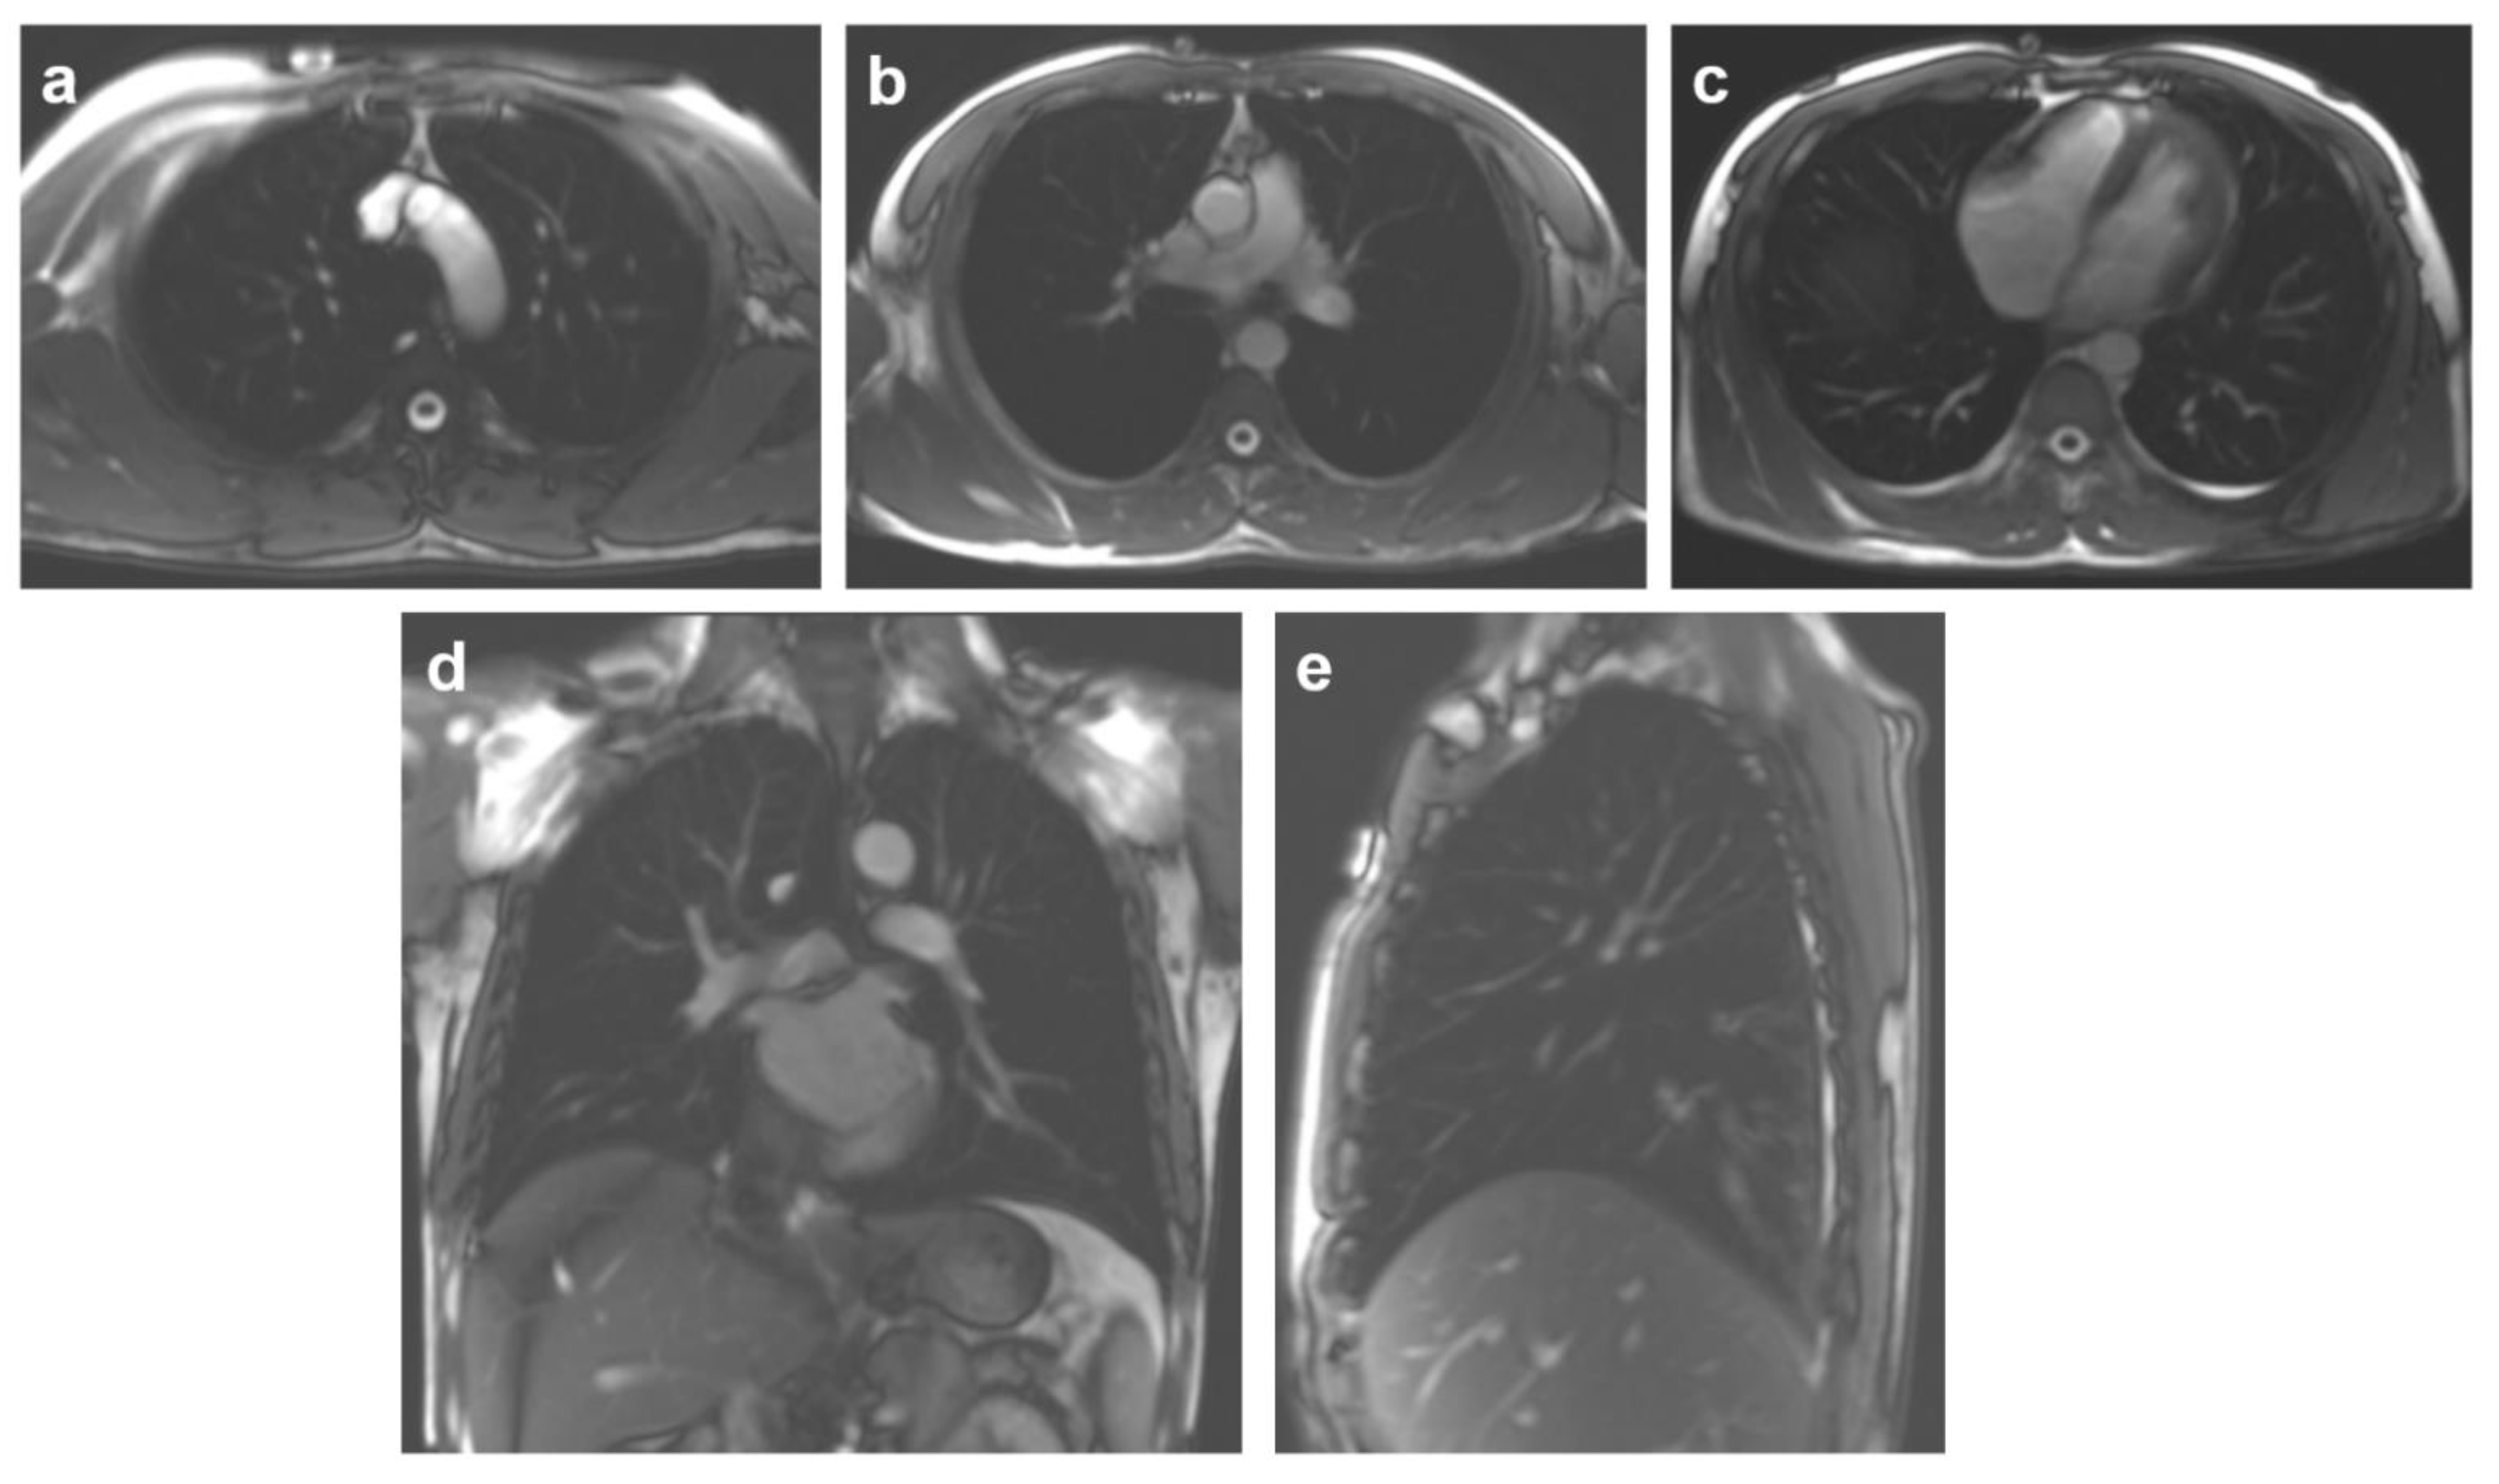

2.3. MRI Protocol

2.4. MR Image Processing and Measurements